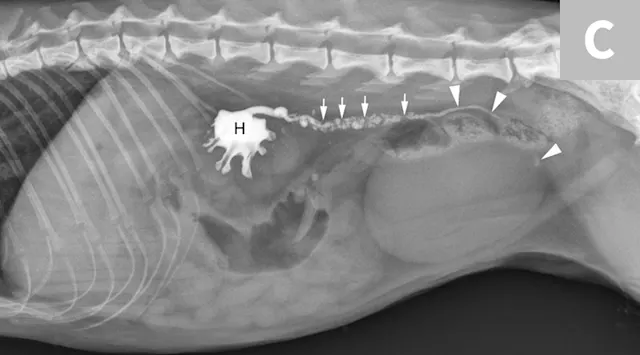

FIGURE 7A

1 / 3

Lateral abdominal radiograph of a cat with multiple, small, oval mineral opacities superimposed over the ventral aspect of the retroperitoneal space (arrows). These mineral opacities are arranged linearly extending from the caudal aspect of the kidneys to the level of the urinary bladder.